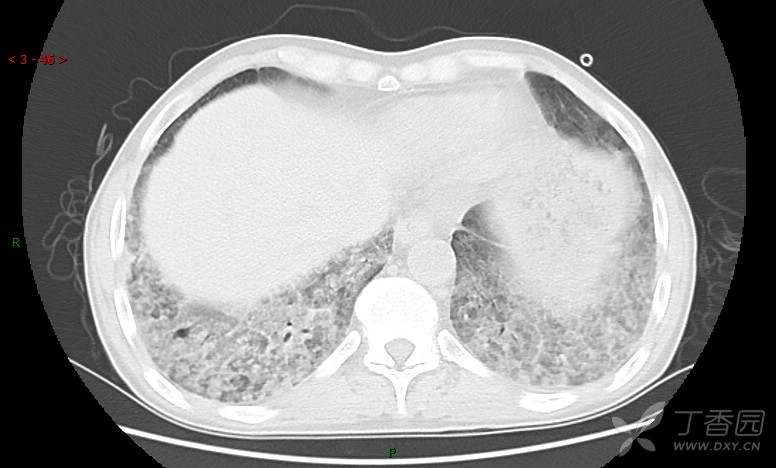

地图+铺路石征=PAP?那升高的CEA怎么说(病例3连发,附其他2例链接)

患者男,42岁,咳嗽半年余,加重伴憋喘2月余。

血清肿瘤相关抗原116.22U/ml↑(0--95);

癌胚抗原 61.96 ng/mL ↑ 0--5

神经特异性烯醇化酶 33.12 ng/ml ↑ 0--16.3

细胞角蛋白19片段测定 40.23 ng/ml ↑ ≤3.3